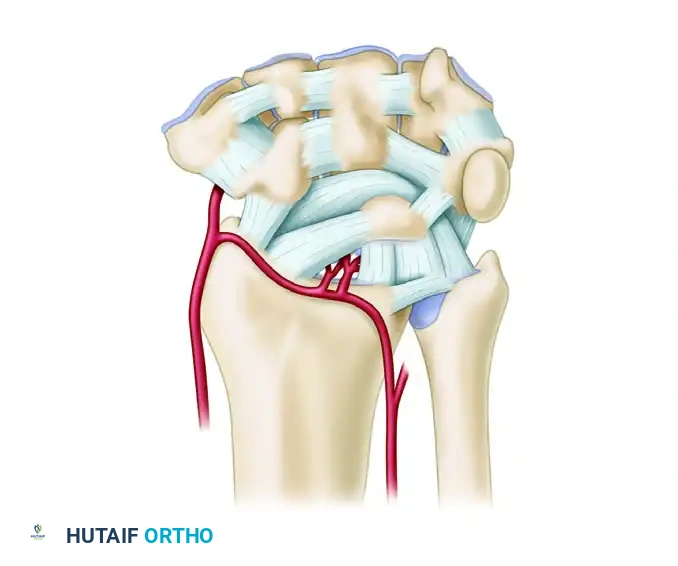

Vascular Anatomy and Circulation

The extraosseous blood supply to the carpus is derived from the terminal branches of the radial, ulnar, and anterior interosseous arteries. These form a highly redundant network of three dorsal and three palmar transverse arterial arches.

Dorsal Arterial Arches

- Dorsal Radiocarpal Arch: Located at the radiocarpal joint; supplies the proximal poles of the scaphoid, lunate, and triquetrum.

- Dorsal Intercarpal Arch: The largest dorsal arch, located between the proximal and distal rows. It supplies the distal carpal row and anastomoses with the radiocarpal arch.

- Basal Metacarpal Arch: Highly variable; supplies the distal carpal row and carpometacarpal joints.

Palmar Arterial Arches

- Palmar Radiocarpal Arch: Supplies the palmar surfaces of the lunate and triquetrum.

- Palmar Intercarpal Arch: Highly variable; rarely contributes significant nutrient vessels to the intraosseous carpus.

- Deep Palmar Arch: Consistent and robust; communicates directly with the dorsal basal metacarpal arch.

Clinical Pearl: The scaphoid and lunate rely heavily on retrograde intraosseous blood flow. The scaphoid receives 70-80% of its blood supply via dorsal ridge vessels entering distally, making proximal pole fractures highly susceptible to avascular necrosis (AVN) and nonunion.